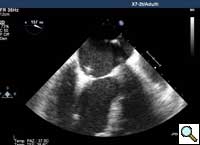

In absence of controlled clinical trial data which are forthcoming from the EVEREST II randomized study, the indications for the MitraClip therapy are currently based on registry experience and will evolve as the technique improves, experience is growing and the data to demonstrate efficacy and safety becomes available. At this time, the best indication for the MitraClip therapy is for symptomatic patients with clinically significant functional or degenerative MR who are at high or increased risk for open heart surgery. From a pure technical standpoint, the procedure so far has only been demonstrated in a subgroup of patients with specific anatomical characteristics which are summarized below and shown in Figure 3. Anatomic suitability is assessed by transesophageal echocardiography, and mitral regurgitation should originate from the central portion of the valve involving the A2-P2 segments, since the device is not ideal to work in the commissures at this time; the mechanism of MR can be either a prolapse/flail or MR due to restricted leaflet motion unrelated to rheumatic disease; the separation between the two leaflets at the site of regurgitation should be limited; severe annular dilatation and/or severe calcification should be absent or is relevant. In case of flail, the flail segment width should be less than 15 mm, and the flail gap less than 10 mm. Figure 4 is a 3D echo image of a patient with posterior leaflet prolapse selected for MitraClip therapy. In case of functional MR, the leaflets should have a minimal residual tissue available for coaptation with the MitraClip device. Figure 5 shows 2D color Doppler jet extension over the coaptation line at TEE short axis transgastric view, while Figure 6 shows the tenting area and the coaptation depth of a patient undergoing MitraClip implant.